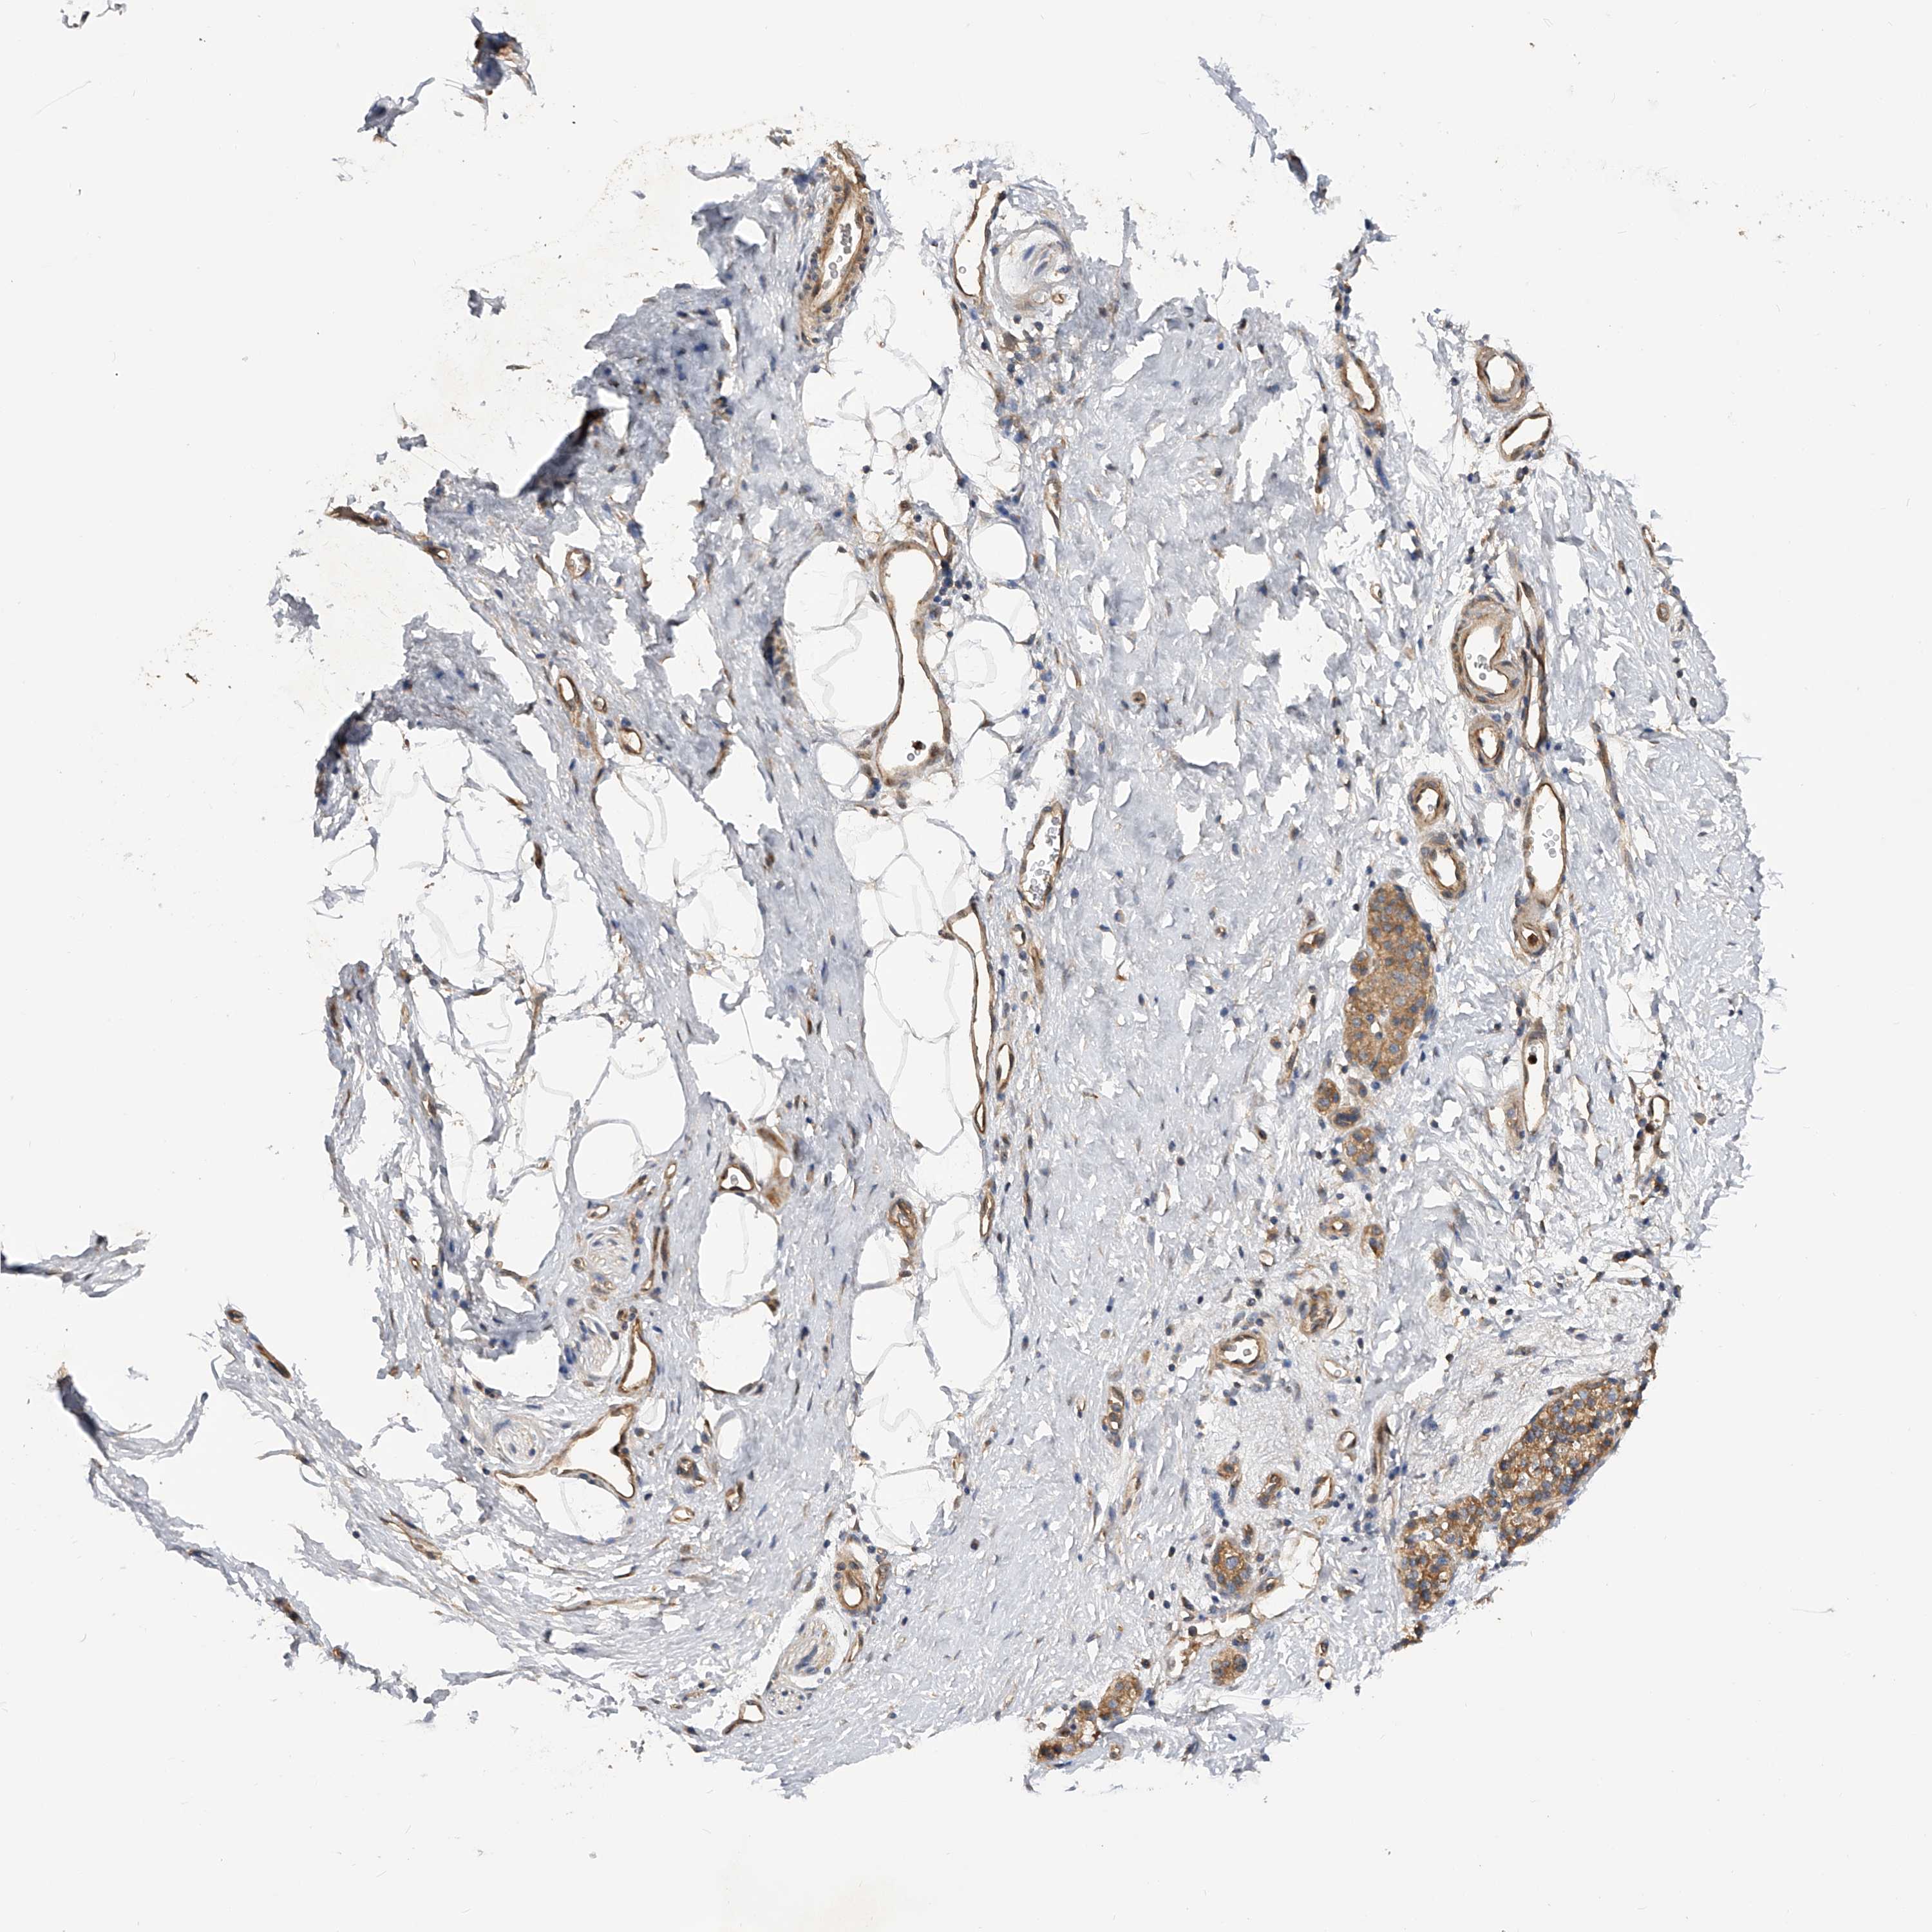

PANCREATIC CANCER - Protein expressioni

A mouse-over function shows sample information and annotation data. Click on an image to view it in a full screen mode. Samples can be filtered based on level of antibody staining by selecting one or several of the following categories: high, medium, low and not detected. The assay and annotation is described here.

Note that samples used for immunohistochemistry by the Human Protein Atlas do not correspond to samples in the TCGA dataset.

Antibody stainingi

Antibody staining in the annotated cell types in the current human tissue is reported as not detected, low, medium, or high, based on conventional immunohistochemistry profiling in selected tissues. This score is based on the combination of the staining intensity and fraction of stained cells.

Each image is clickable and will lead to virtual microscopy that enables deeper exploration of all samples and also displays staining intensity scores, fraction scores and subcellular localization as well as patient and tissue information for each sample.

Antibody HPA029412

Antibody CAB034366

Staining

High

Medium

Low

Not detected

Intensity

Strong

Moderate

Weak

Negative

Quantity

>75%

75%-25%

<25%

None

Location

Nuclear

Cytoplasmic/membranous

Cytoplasmic/membranous,nuclear

Adenocarcinoma, NOS